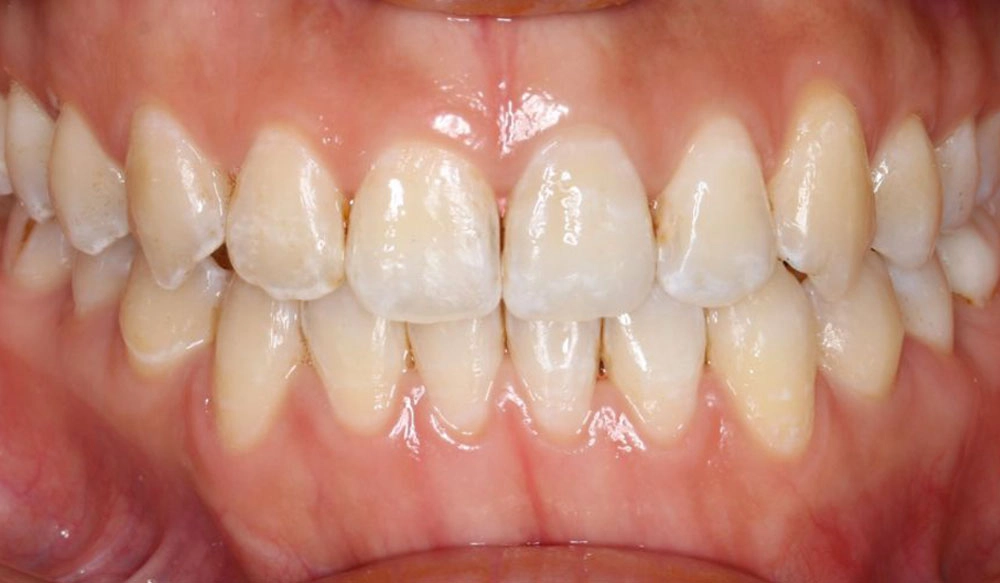

Chen chúc

Chen chúc là tình trạng có sự chênh lệch giữa kích thước răng và không gian có sẵn để sắp xếp răng trên cung răng.

Thông tin bệnh nhân:

Tuổi: 17

Giới tính: nữ

Lựa chọn điều trị Invisalign: Invisalign Comprehensive

Tổng thời gian điều trị:

29 tháng